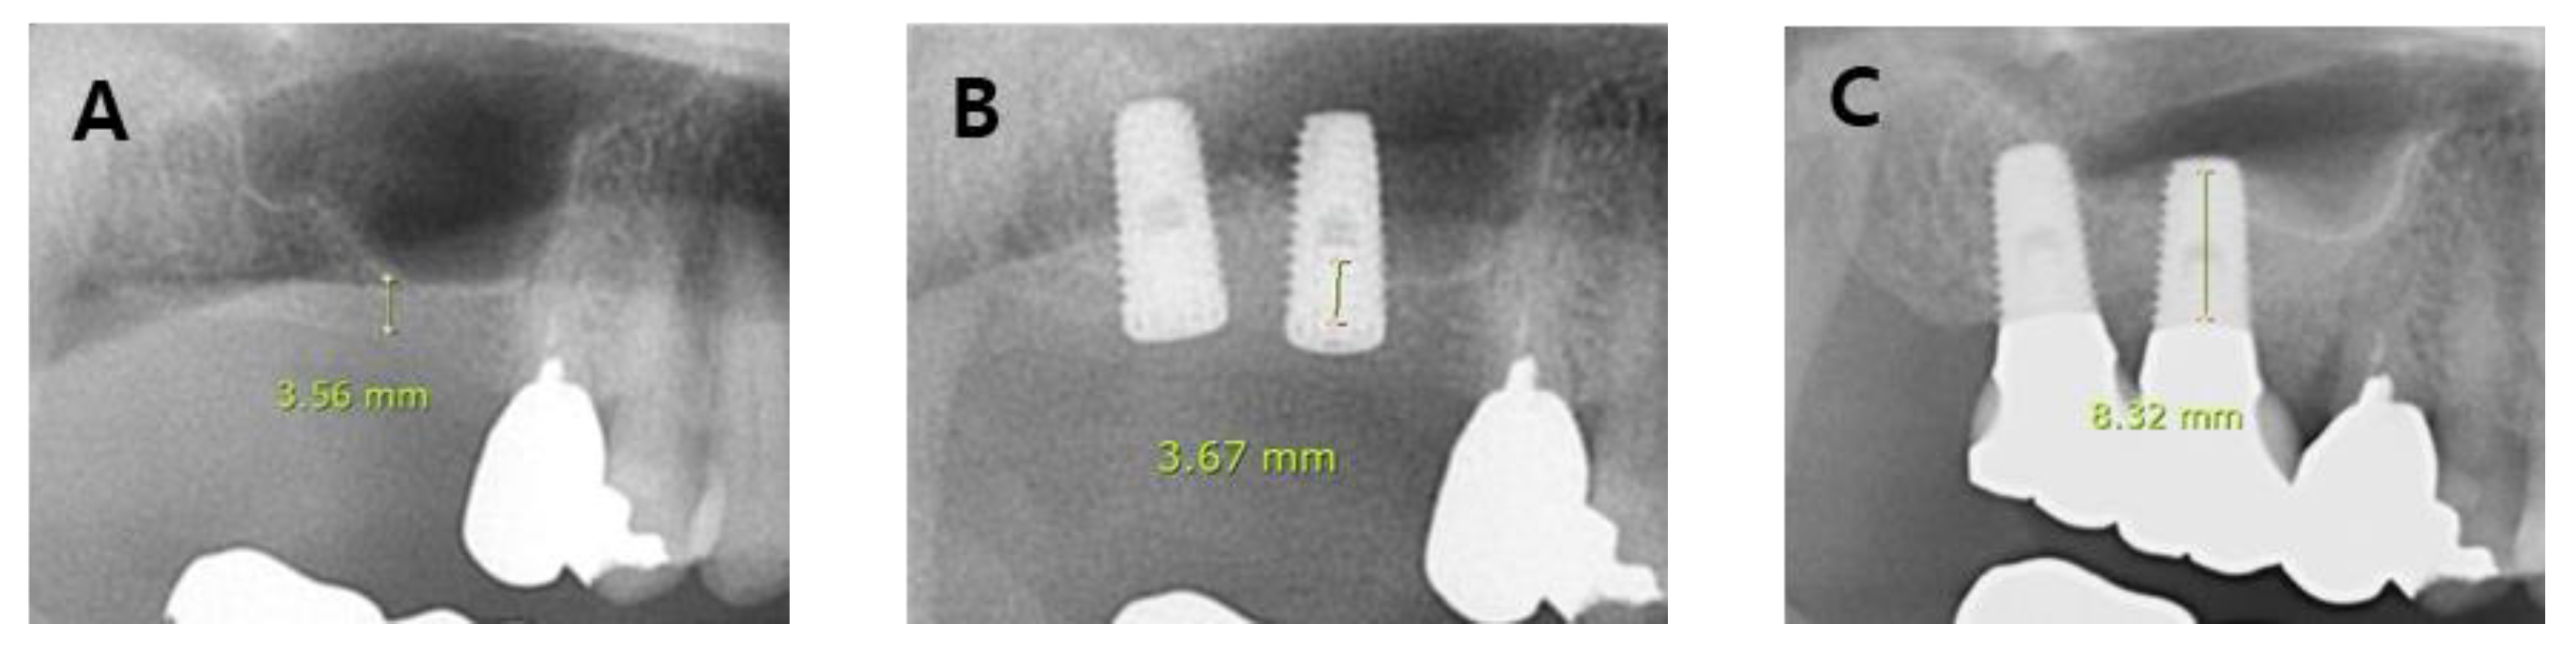

- (A)

- Group 1: No SMP but the membrane was weakened (or thinned) during sinus lift procedure;

- (B)

- Group 2: SMP was small to medium in size (< 10 mm) during sinus lift procedure;

- (C)

- Group 3: SMP was large in size (> 10 mm) during sinus lift procedure;

| Group | Pre op | Post op | Follow-up | Source: F(p) |

| 1 | 4.08 ± 2.55 | 14.94 ± 3.00 | 13.00 ± 2.40 | Group: 52.97 (<.001) Time: 203.67 (<.001) Group*Time: 11.67 (<.001) |

| 2 | 4.92 ± 2.55 | 13.81 ± 3.61 | 12.65 ± 3.43 | |

| 3 | 3.88 ± 2.21 | 3.82 ± 2.19 | 4.99 ± 2.59 | |

| Control | 5.53 ± 3.29 | 16.00 ± 3.63 | 13.22 ± 4.09 |